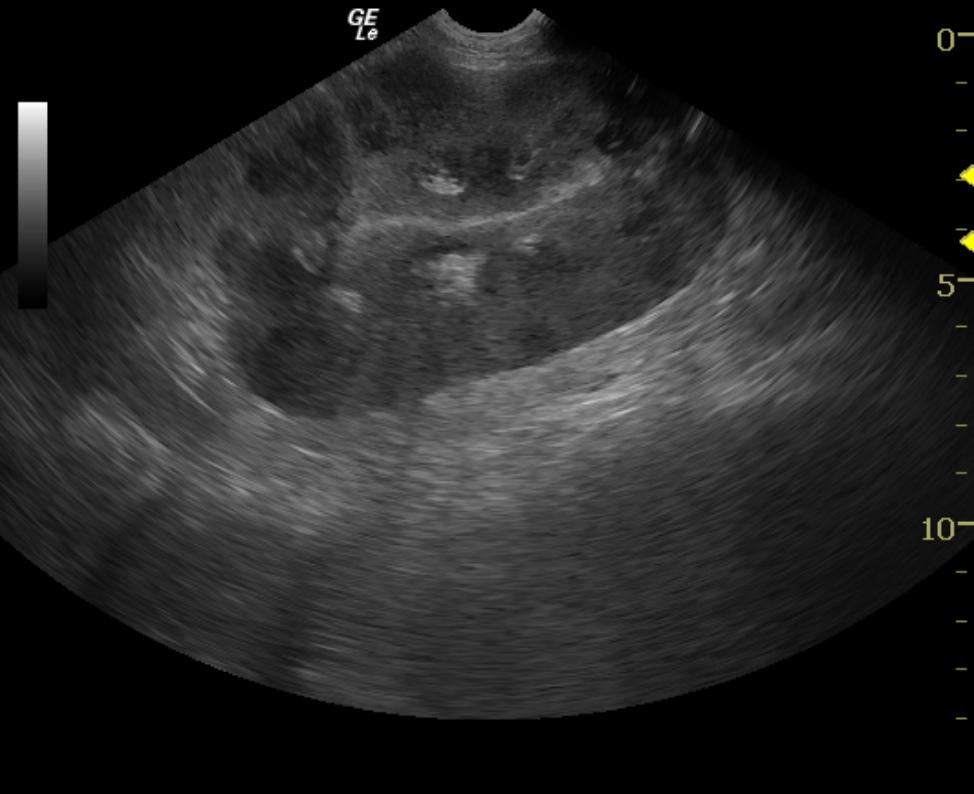

A 6-year-old female spayed Labrador Retriever dog was presented with upper gastrointestinal signs of 2 days’ duration. The patient was treated with antibiotics, gastroprotectants, and anti-emetics. Upper gastrointestinal signs continued despite the treatments, and the dog developed excessive panting and shaking. Blood chemistry revealed azotemia, hyperalbuminemia, and hyperphosphatemia. CBC revealed elevated hematocrit and elevated hemoglobin. Abdominal radiographs did not reveal any abnormalities. The dog was treated with IV fluids, however her azotemia continued to worsen despite treatment.